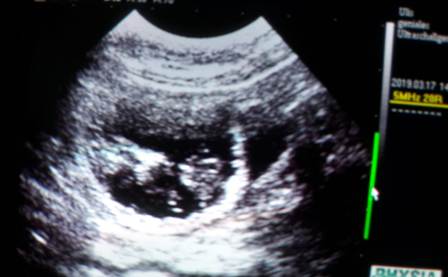

Hier die ersten Bilder unserer Kindlys:

Zählen war noch nicht möglich, sie zu erwischen war schon schwer ;) ;)

Ich denke wir konnten ca. 5 gut sehen..

Aber das heißt noch gar nichts!

Im Laufe der Woche, so um den 25-28 Tag, werde ich noch einmal schallen.

Erst danach, werde ich mich bei allen melden!

Wir freuen uns soo sehr!!!